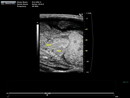

Caption Play MovieUltrasound imaging of mutant 012-003-2 in the sagittal view reveals single outflow tract